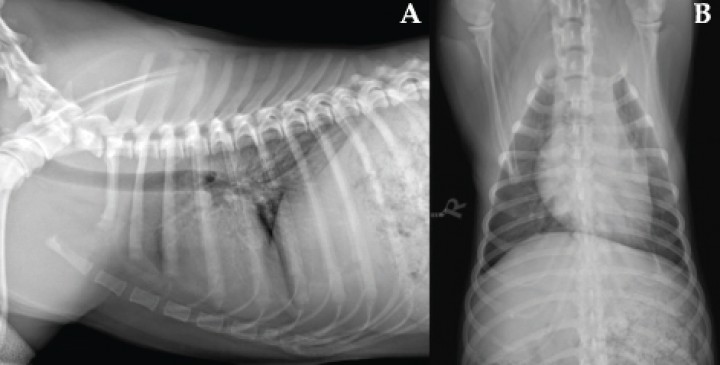

En este caso se optó por un tratamiento conservador, consiguiendo una evolución favorable, tal como se observa en las radiografías de control (Figs. 4 y 5). Aunque no se dispone de confirmación histopatológica, la evolución clínica y radiológica refuerza el diagnóstico de hematoma tímico, hemotórax y hemorragia pulmonar difusa.

<p>Radiografías realizadas a los 4 días. (<strong>A</strong>) Proyección laterolateral derecha. (<strong>B</strong>) Proyección ventrodorsal. Se aprecia reducción de tamaño de la masa mediastínica y resolución casi completa de la hemorragia pulmonar, con persistencia leve de patrón intersticial difuso y leve efusión pleural.</p>

Radiografías realizadas a los 4 días. (A) Proyección laterolateral derecha. (B) Proyección ventrodorsal. Se aprecia reducción de tamaño de la masa mediastínica y resolución casi completa de la hemorragia pulmonar, con persistencia leve de patrón intersticial difuso y leve efusión pleural.